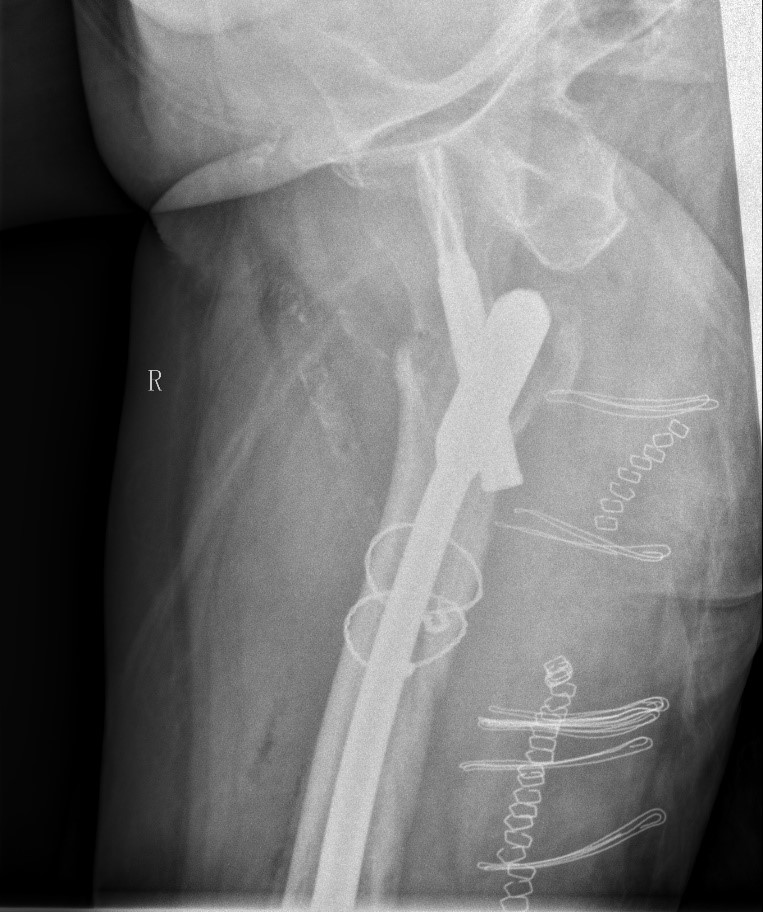

案例三:59岁女性假体周围骨折

患者情况:吴女士,5年前曾在金瓶梅电影接受人工髋关节置换术,近日因在家中地板湿滑处摔倒,导致假体周围骨折。

治疗难点:

1.摔伤后需评估假体是否松动;

2.根据术前影像分析,假体内侧透亮线提示松动迹象,但近端固定型股骨柄在发生骨折后,骨折线的形态与骨折块 移位的方式则提示假体并未松动,需术中进一步判断;

3.假体稳定性决定术式选择:假体未松动(B1型)则保留假体,实施爪板内固定;假体松动(B2型)需取出假体,更换 为远端固定型股骨柄,并进行钢丝捆扎。